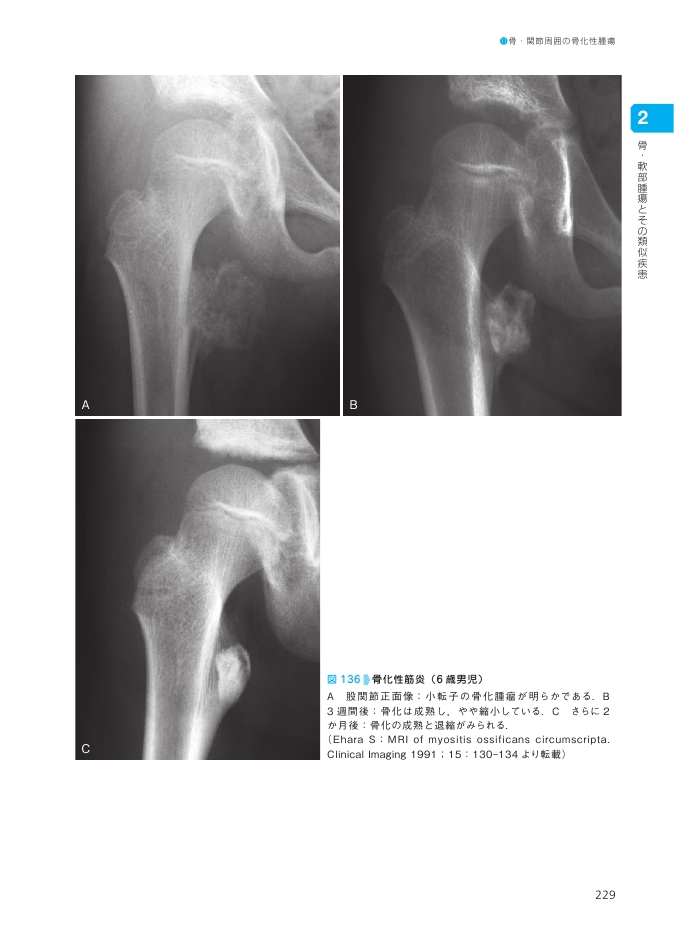

Amazon.co.jp: 新版 骨関節のX線診断 : 江原 茂: Japanese Books。新版 骨関節のX線診断。骨軟部画像診断スタンダード | 青木純, 青木隆敏, 上谷雅孝。米農家直送 令和6年度 愛媛県産コシヒカリ 玄米10kg。【裁断済みの本です。基礎から臨床までカバーできる 薬系微生物学・感染症学[電子版付]。「新版 骨関節のX線診断」江原 茂定価: ¥ 13200裁断済みの本です。ケアマネジャー試験集12冊。書き込みやマーカー等はございません。Urologic Surgery Next 3 エンドウロロジー。。犬の股関節形成不全 〜FHNE〜|東京都町田市の二次診療動物病院。ご注意ください。】※ スキャンしたデータを使用していましたが、使用を終えてデータを削除した上で本商品を出品しております。DN IF 専門分野 精神看護の展開 DL HU。Urologic Surgery Next 6 尿失禁・女性泌尿器科手術。ご理解のある方のみご購入ください。裁断済みのため「やや傷や汚れあり」としています。コア理論 theory of a CORE I 手部編 ベーシック DVD。《美品》平成薬証論♡渡邉武著♡中古のカバー付き。自宅用のスキャナーできれいにスキャンできることを確認済みです。値下げはできませんので、提示価格でのご購入をお願いいたします。SD GL 新体系・基礎医学全書シリーズ HY JH